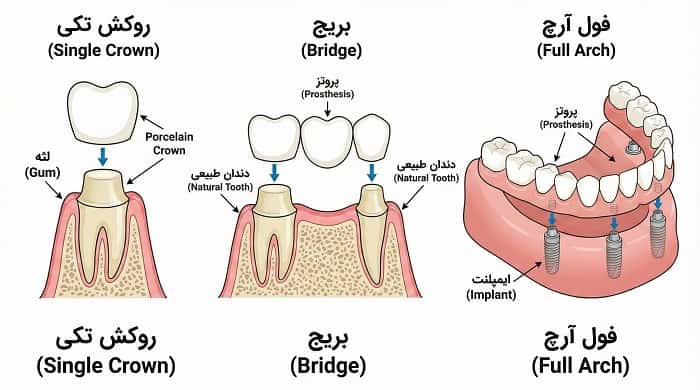

انواع پروتز ثابت روی ایمپلنت زمانی که یک یا چند دندان از دست میرود، ایمپلنت دندانی این امکان را میدهد که جایگزینی نزدیک به دندان طبیعی ایجاد شود. اما آنچه بیمار در نهایت میبیند و با آن میجوَد، پروتز ثابت روی ایمپلنت است؛ یعنی روکش یا پروتزی که روی ایمپلنت سوار میشود و شکل و عملکرد دندان را بازسازی میکند. شناخت انواع پروتز ثابت روی ایمپلنت به دندانپزشک کمک میکند برای هر بیمار، گزینهای متناسب با شرایط استخوانی، نیاز زیبایی و الگوی فانکشن انتخاب کند.

پروتز ثابت روی ایمپلنت، ترمیمی است که پس از قرار گرفتن روی ایمپلنت، توسط بیمار خارج نمیشود و مانند دندان طبیعی حس ثبات و استحکام ایجاد میکند. این پروتزها میتوانند از یک روکش تکی تا یک فول آرچ کامل متکی بر چند ایمپلنت را شامل شوند. مزایای اصلی عبارتاند از:

روکش تکی (Single Crown)

سادهترین نوع پروتز ثابت ایمپلنتی، روکش تکی است. در این حالت، یک ایمپلنت جایگزین ریشه دندان از دست رفته میشود و روی آن یک روکش به شکل دندان طبیعی قرار میگیرد. این روش معمولاً زمانی انتخاب میشود که یکی دو دندان جداگانه از دست رفته باشند و سایر دندانها سالم یا قابل حفظ باشند. روکش تکی روی ایمپلنت میتواند از نظر شکل و رنگ بهخوبی با دندانهای مجاور هماهنگ شود.

بریج ثابت متکی بر ایمپلنت

وقتی چند دندان کنار هم از دست رفتهاند، میتوان با استفاده از دو یا چند ایمپلنت، یک بریج ثابت ساخت که چند دندان را همزمان جایگزین کند. این روش گاهی اجازه میدهد بهجای کاشت ایمپلنت جداگانه برای هر دندان، با تعداد کمتری ایمپلنت کل فضا بازسازی شود. طراحی بریج باید به گونهای باشد که نیرو بهصورت متعادل بین ایمپلنتها توزیع شود و طول کانتیلیور کنترل گردد.

پروتز فول آرچ ثابت روی ایمپلنت

در بیماران بیدندان، پروتز کامل فک بالا یا پایین میتواند بهصورت فول آرچ ثابت روی چند ایمپلنت اجرا شود. این نوع پروتز، جایگزین دست دندان متحرک است و از نظر فانکشن و ثبات، تجربه کاملاً متفاوتی برای بیمار فراهم میکند. ساختار فول آرچ ممکن است هیبرید فلز–آکریل، زیرکونیا یا ترکیبی از متریالها باشد. توضیحات تکمیلی در مقاله فول آرچ روی ایمپلنت بهصورت اختصاصی ارائه شده است.

انواع پروتز ثابت روی ایمپلنت، طیفی از روکش تکی تا بریج و فول آرچ را دربر میگیرد و هر کدام اندیکاسیونها، مزایا و محدودیتهای خاص خود را دارند. انتخاب نوع پروتز، نوع اتصال (اسکرو رتین یا سمان رتین) و متریال، زمانی منطقی و قابل دفاع است که بر پایه تحلیل دقیق شرایط بیمار، طرح درمان و همکاری نزدیک با لابراتوار تخصصی دیجیتال انجام شود. نتیجه این فرآیند، پروتزی است که از نظر فانکشن، زیبایی و دوام، بیشترین انطباق را با اهداف درمانی دارد.